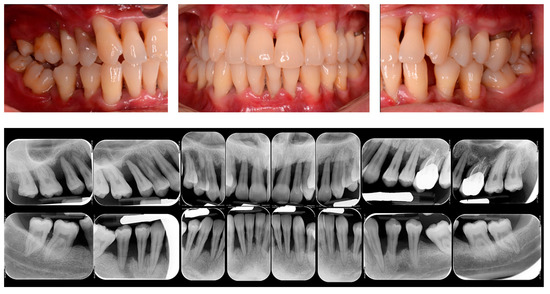

The success of periodontitis therapy, both in the short- and long term, depends on the effect of physical disintegration of the supra and subgingival periodontal pathogens presented in the biofilm [24]. The initial causal therapy mainly consisted of oral hygiene instruction and professional scaling and root planing (SRP). Both the supra- and subgingival pathogens and calculus are mechanically disrupted, with combined and synergic effects induced by periodontal debridement and domiciliary oral hygiene instructions [25]. In this regard, the gold standard of non-surgical therapy of periodontitis is represented by the SRP performed by both hand and ultrasonic instruments alone, with a demonstrated microbial and clinical effectiveness in the short-term period [26,27] (Figure 1).

Figure 1.

Clinical and Rx images of a patient with periodontitis.

It has been previously shown that the mechanical disruption of supra- and subgingival biofilm by the non-surgical periodontal therapy performed by SRP alone can reduce the plaque index (PI) and the bleeding on probing (BOP) in around 45% of periodontal sites [28]. On this regard, following non-surgical periodontal therapy, a reduction in the probing depth (PD) has been demonstrated in a range of 1.29 mm for periodontal pockets with an initial PD of 3–4 mm and of 2.2 mm for the pockets ranged 5–6 mm and an improvement in the clinical attachment level (CAL) in a range of 0.5–2 mm [29,30].